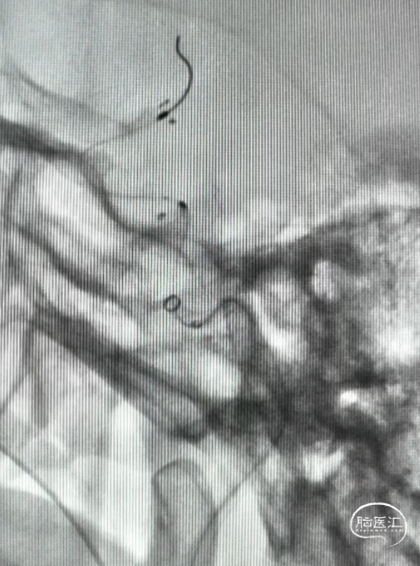

DCwire®微导丝通过闭塞段

微导管到达闭塞段以远真腔

释放4.0*30mm Syphonet®取栓支架

2.5*15mm SacSpeed®球囊扩张导管在C5段进行球囊扩张

2.5*15mm SacSpeed®球囊扩张导管在C1段进行球囊扩张

清理管腔血栓

回收4.0*30mm Syphonet®取栓支架

置入4.0*20mm 颅内支架

术后成形良好